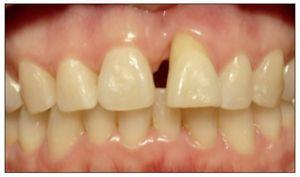

Figura 1. Visible discrepancia estética en posicion del margen gingival entre piezas 8 y 9.

Figura 8. Discrepancia severa en posición de margen gingival entre piezas 8 y 9.